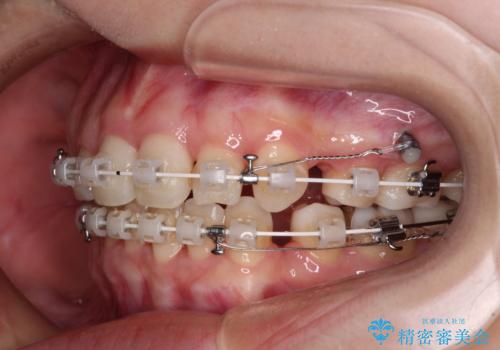

上下前歯が非接触である開咬は、インビザラインによる治療がお勧めではありますが、非抜歯矯正か抜歯矯正か悩む口元であり、途中抜歯矯正に切り替えたときに対応しやすいよう、ワイヤー装置にて治療を行うこととしました。

舌の突出癖の影響もあり、非抜歯矯正で治療開始したものの口元が突出し、唇が閉じにくくなってしまったため、途中で第一小臼歯4本を抜歯ししました。